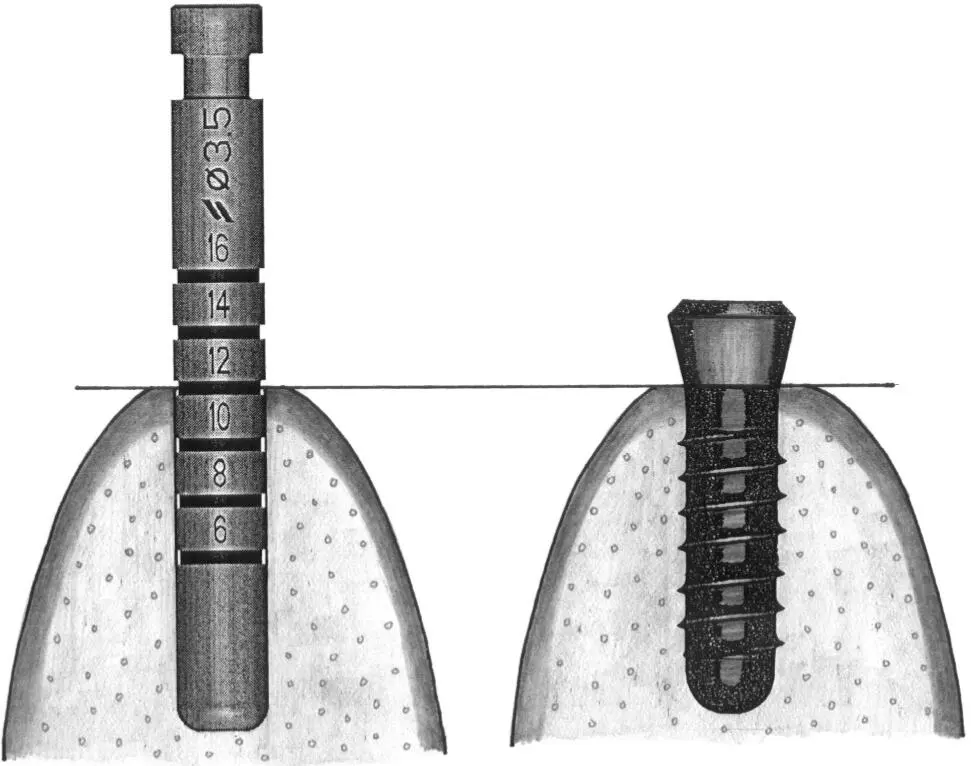

Fig 1-5Varying sink depths.

Fig 1-5a The 3.5-mm-diameter depth gauge is inserted so that the middle of the 12-mm mark is aligned with the bone crest (left) . When the standard implant is inserted, this allows the rough border to be aligned exactly at the crest (right) .